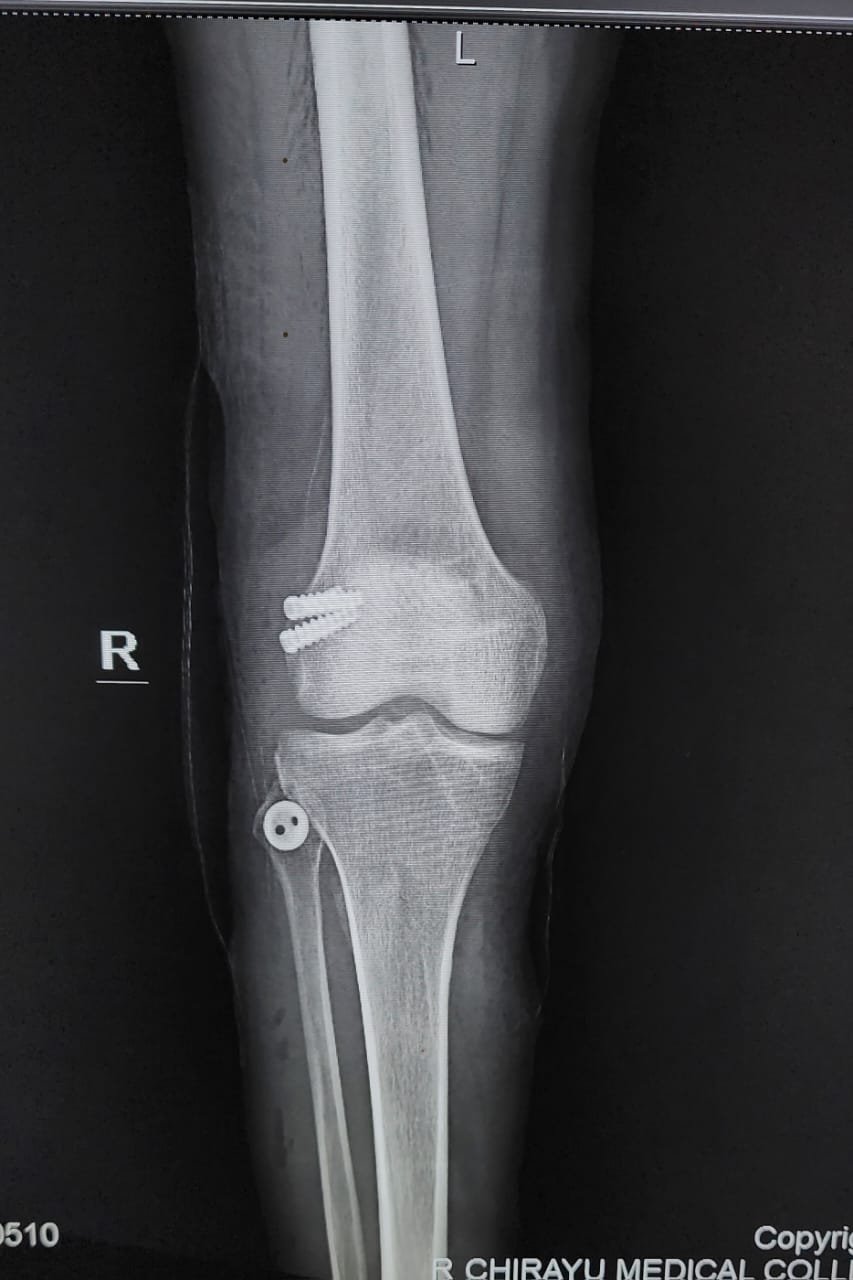

- ACL Reconstruction

- PCL Reconstruction

- Meniscus Repair

- Arthroscopy-Knee

- Fracture Treatment